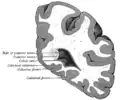

Корональный срез через задние рога боковых желудочков.

Корональный срез через передние рога боковых желудочков.

Боковой срез человеческого мозга.